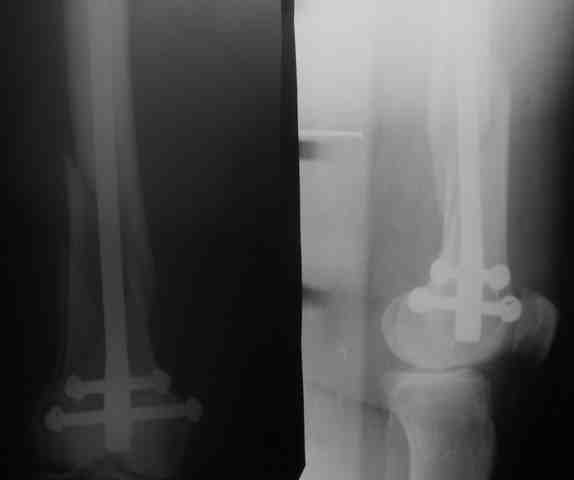

Рг в приложении.

КАН> допущенные ошибки. Спасибо. Рг в приложении.

Снимки вполне симпатичные. Единственное, по ротации не понял, уж больно неразборчивый тот, который без гвоздя.